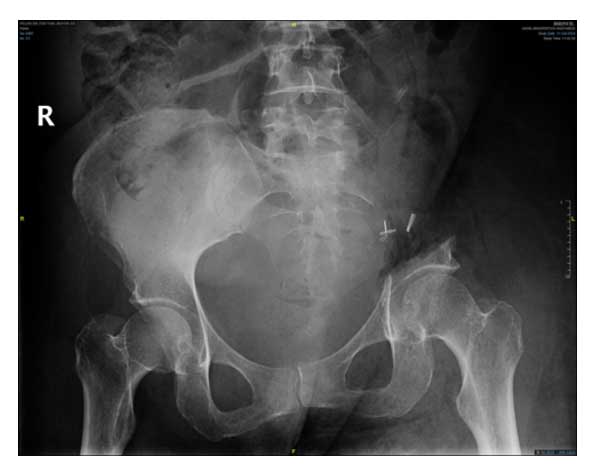

Ameliyat Sonrası: Röntgende ol sakroiliak rezeksiyon görülmekte.